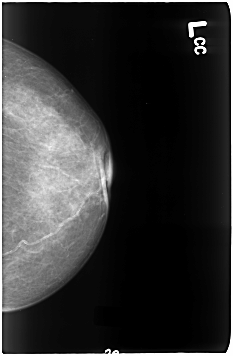

B_3050_1.LEFT_CC

LEFT_CC LINES 4616 PIXELS_PER_LINE 3024 BITS_PER_PIXEL 12 RESOLUTION 50 NON_OVERLAY

LEFT_MLO LINES 4632 PIXELS_PER_LINE 3008 BITS_PER_PIXEL 12 RESOLUTION 50 NON_OVERLAY